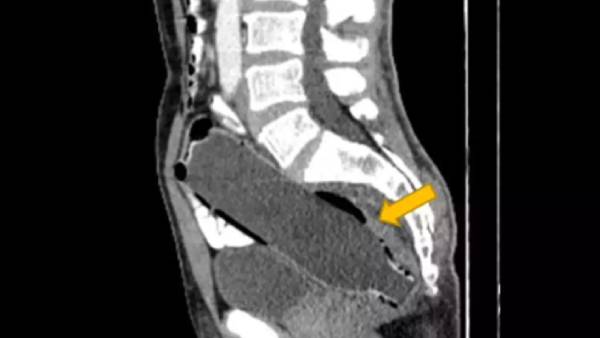

அப்போதும் நடந்தது என்ன என்பதை மருத்துவரிடமோ அல்லது தன் மனைவியிடமோ அந்தக் கணவர் கூறவில்லை. மருத்துவரிடம் சரியாக மலம் கழிக்க இயலவில்லை, பசிக்கவில்லை என்று மட்டும் திரும்பத் திரும்ப அவர் கூறியிருக்கிறார். எனவே, அந்தக் கணவரின் உடலில் என்ன பிரச்சினை எனத் தெரிந்து கொள்வதாக, அவரது வயிற்றுப்பகுதியை ஸ்கேன் செய்து பார்த்துள்ளனர் மருத்துவர்கள்.

அப்போது அவரது ஆசனவாயில் வாட்டர்பாட்டில் ஒன்று சிக்கியிருப்பதைப் பார்த்து அவர்கள் அதிர்ச்சி அடைந்தனர். 250 மிலி நீரை நிரப்பும் 19 செமீ நீளம் இருந்த அந்த பாட்டில் எப்படி ஆசனவாயில் சிக்கியது என்பதை, கையும் களவுமாக மாட்டியபிறகும், அந்தக் கணவர் கூற மறுத்துள்ளார். அவருக்கு தன் ஆசனவாயில் வாட்டர்பாட்டில் இருப்பது தெரிந்தும், அதைத் தன் மனைவியிடம் கூறினால் அவர் நிச்சயம் திட்டுவார் என அவரிடம் மறைத்து வந்துள்ளார்.